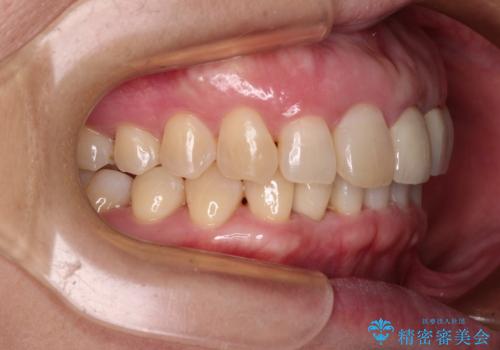

- 下顎前歯が抜けそうとのことで来院された患者様です。

初診の状態ではすぐにでも抜けそうな状態で、インプラントによる補綴治療を行うこととしました。

インプラント治療に際し、前歯の叢生に対する矯正治療を提案したところ、興味を持たれたので、インビザライン・ライトによる矯正治療を行うこととしました。

抜歯後にスペースができると恥ずかしいため、抜歯した歯を接着剤で固定した上で矯正治療を行い、その後インプラントやオールセラミッククラウンの装着を行うこととしました。